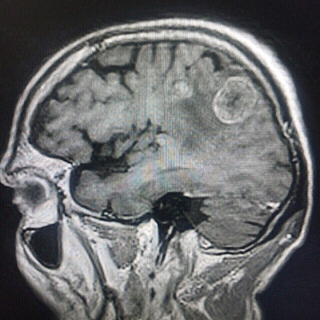

О ПРОТИВОПОКАЗАНИЯХ ПРОКОНСУЛЬТИРОВАТЬСЯ СО СПЕЦИАЛИСТОМ Открыта запись на Магнитно-резонансную томографию. Тел. для записи 7-40-66. Стеклозаводское шоссе, поликлиника на территории стекольного завода. Общая информация.Магнитно-резонансная томография (МРТ) — принципиально отличающийся от рентгеновского исследования или компьютерной томографии метод диагностики. Для получения изображения магнитно-резонансный томограф (МРТ) не использует рентгеновское излучение. Пациента помещают в магнитное поле, которое образует МР томограф. Поэтому в названии этого метода присутствует слово «магнитный». Затем в долю секунды аппарат испускает радиочастотный импульс, и молекулы тканей человека вступают в резонанс. Поэтому томография не просто магнитная, а магнитно-резонансная. Ядра атомов испускают ответные колебания, их регистрирует компьютер, томограф распознает эти сигналы, дешифрует их и строит изображение среза органа или части тела. МРТ позволяет, избегая рентгеновского облучения, представить в снимках все тело человека. МРТ «видит» мягкие ткани: мышцы, нервы, мозг, позвоночник и межпозвоночные диски, связки и т.д. Эта технология позволяет получать снимки изнутри тела в трехмерном изображении. Магнитно-резонансная томография является незаменимым и ведущим современным методом исследования структуры головного мозга, позвоночника, органов брюшной полости, малого таза, суставов (коленные, тазобедренные). Магнитно-резонансная томография безвредна! Процедура представляет собой исследование продолжительностью от 10 до 40 минут в зависимости от области обследования, во время которого пациент должен лежать абсолютно неподвижно. В МР-томографе применяется магнитное поле, не причиняющее вреда здоровью. Для исследования в Медицинском центре «Гарантия» используется магнитно-резонансный томограф Siemens Magnetom тунельного типа. Ваш лечащий врач назначил Вам исследование на МР-томографе. МРТ позволяет получать отчетливые изображения внутренних органов, помогает установить диагноз и назначить правильное лечение. Метод МРТ весьма эффективен в диагностике большинства заболеваний головного мозга, головы и шеи, спинного мозга и позвоночника, органов малого таза, суставов и мягких тканей конечностей. Направление на МРТ не обязательно означает, что у Вас имеется какое-либо заболевание – возможно, врач желает уточнить состояние Вашего здоровья. МРТ головы Показаниями к МРТ головы являются: